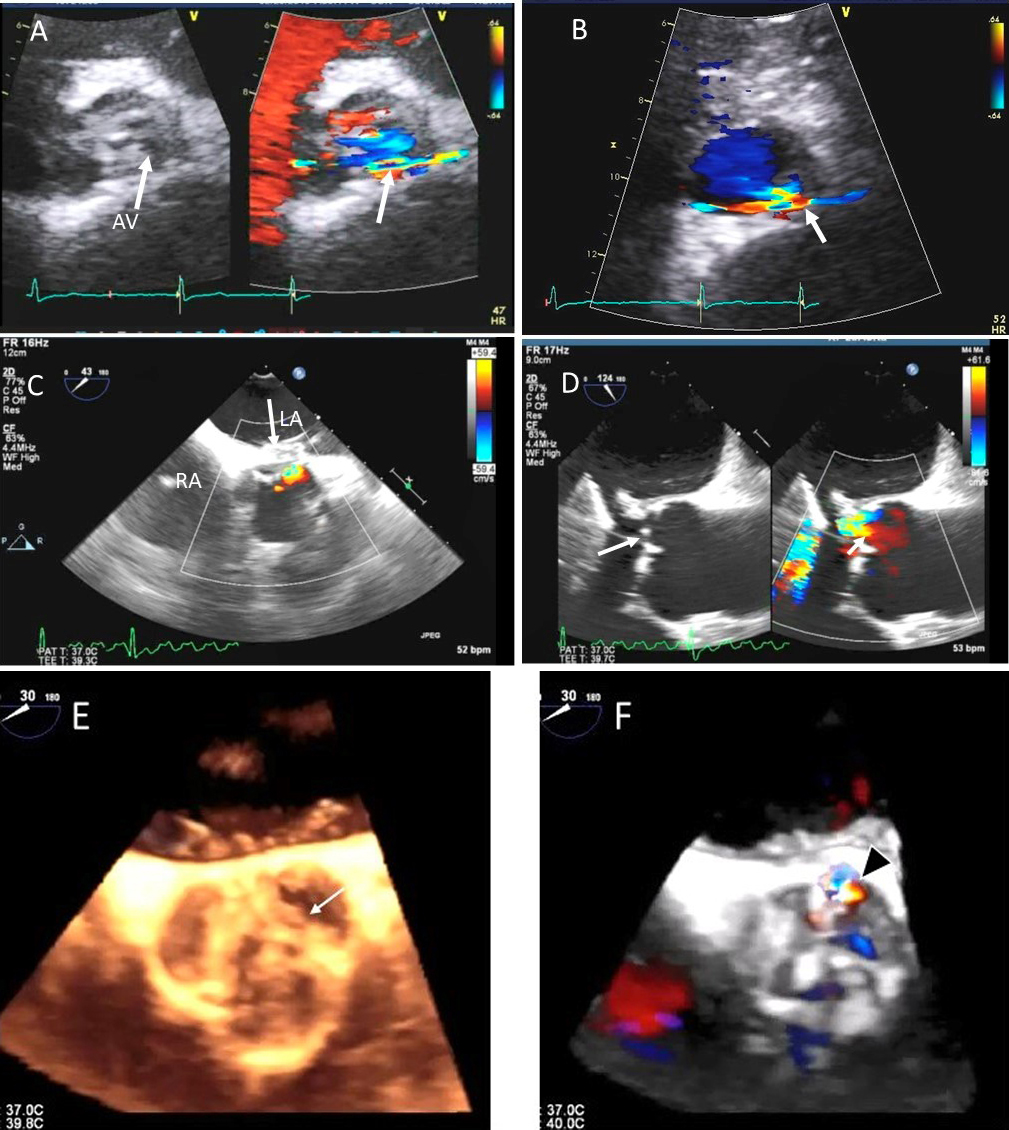

Fig. 9.Aortic valve regurgitation induced by dilated annulus. (A)

Transthoracic echocardiogram parasternal long axis view showing

markedly dilated aortic sinuses (red arrow). (B) Imaging at a higher parasternal window shows aneurysmal aortic sinuses (red arrow)

and normal ascending aorta above sinotubular junction.

(C) Three chamber view with continuous-wave (CW) Doppler showing dense AI Doppler

envelope with a steep deceleration slope (red arrows) suggesting severe AI. (D) CW Doppler recording at the proximal descending thoracic aorta

demonstrating pandiastolic flow reversal (red arrows), another feature of severe AI.

(E) Color Doppler parasternal long axis view showing AI color

jet occupying two third of the LV outflow tract with a wide vena contracta at origin from the aortic valve leaflets (